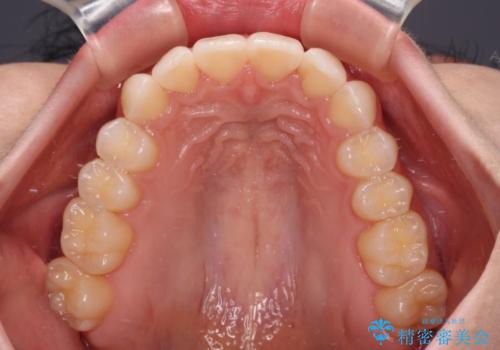

前歯のデコボコと深い咬み合わせ インビザラインできれいに改善

インビザラインによる上下歯列の拡大と、IPR(歯と歯の間を削る)にるスペースの獲得により、口元のデコボコとディープバイトを改善することとしました。

インビザラインは、装着していない時間がどれだけ短いかが、治療期間を大きく左右します。こちらの患者様は1日22時間以上、毎日欠かさず装着してくださったため、1年弱という短期間で満足のいく歯列に整えることができました。